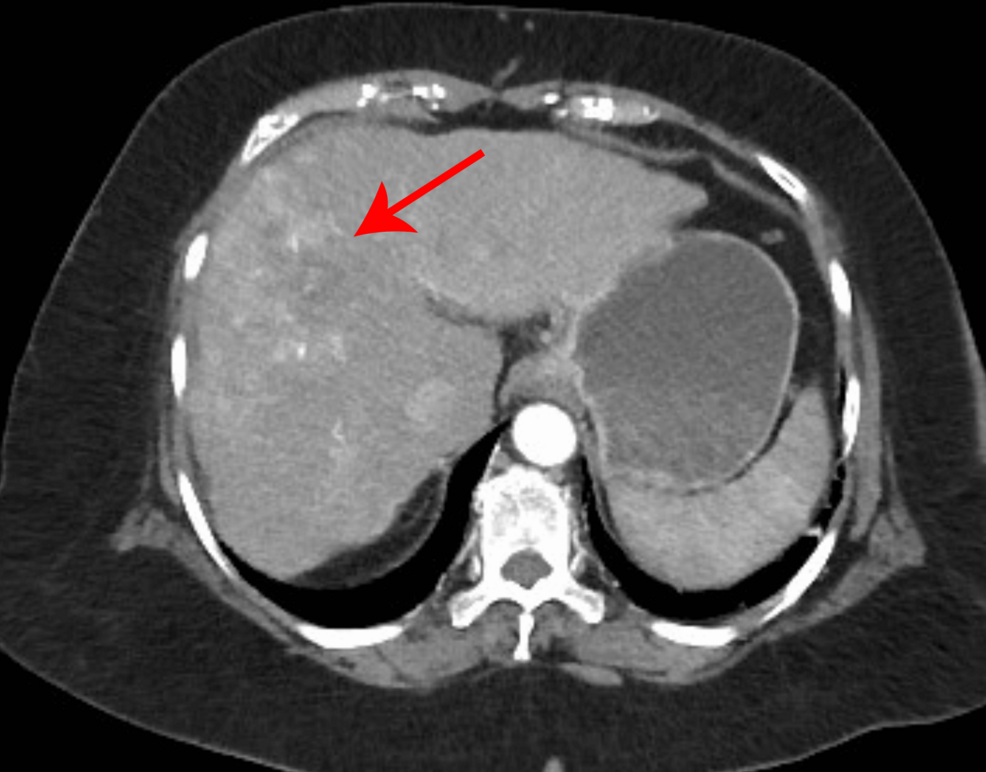

Clinical Case Study: Rapid Skeletal Progression

A 62-year-old male with a history of chronic hepatitis B presented with progressively worsening bone pain in his lower back and left hip. Initial diagnosis six months prior was Stage II HCC, treated with partial hepatectomy. Post-operative surveillance imaging showed no evidence of recurrence for the frist three months. However, subsequent scans revealed multiple lytic lesions in the lumbar spine, pelvis, and femur – indicative of bone metastasis.

The progression from initial recurrence detection to widespread bone involvement occurred within just six weeks – classified as rapid bone metastasis.This case highlights the aggressive potential of HCC and the importance of vigilant monitoring.

Computed Tomography (CT): Useful for assessing cortical bone destruction and identifying associated lung or lymph node metastases.